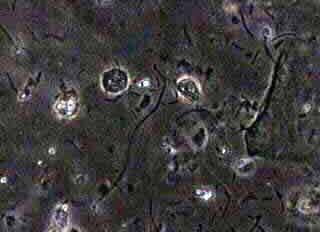

Σε μιά αντικειμονοφόρο πλάκα τοποθετούμε μιά σταγώνα φυσιολογικού ορού. Με μια ψήκτρα λαμβάνουμε μικρό δείγμα κολπικού εκκρίματος, το ανακατεύουμε με τον φυσιολογικό ορό, τοποθετούμε μία καλυπτρίδα και το εξετάζουμε αμέσως με κοινό μικροσκόπιο, σε μεγεθύνσεις 10Χ10 και 10Χ40, με στενή δέσμη φωτός, δηλαδή με κλειστό το διάφραγμα του μικροσκοπίου. Αν υπάρχει δυνατότητα για αντίθετες φάσεις φωτός, οι εικόνες είναι καλλίτερες. Γενικά όμως επαρκεί και ένα απλό μονοφθάλμιο μικροσκόπιο.

Εύκολα διακρίνουμε τα γνωρίσματα της μυκητιάσεως:

Ψευδομυκητήλια και ενδεχομένως χλαμυδοσπόρια.

Nωπά παρασκευάσματα σε κολπίτιδα εκ μονιλιάσεως.

Ψευδομυκητήλια, 10χ10

Ψευδομυκητήλια, 10Χ40